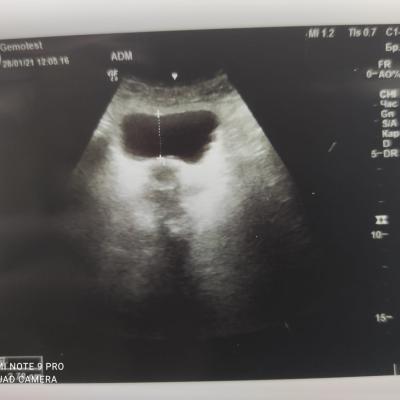

Здравствуйте! При наличии коралловидного камня правой почки(заключение УЗИ), можно предположить причиной боли нарушение уродинамики верхних мочевых путей), что, однако, не подтверждается результатами УЗИ почек( ЧЛС не расширена). Другая, наиболее вероятная возможная причина "боли в боку" - может быть патология опорнодвигательного аппарата. Необходимо проконсультироваться с неврологом и урологом очно, и согласовать возможность применения противовоспалительных, обезболивающих и спазмолитических препаратов - как первый шаг. В дальнейшем необходимо планировать возможное дальнейшее обследование и лечение. Удачи!